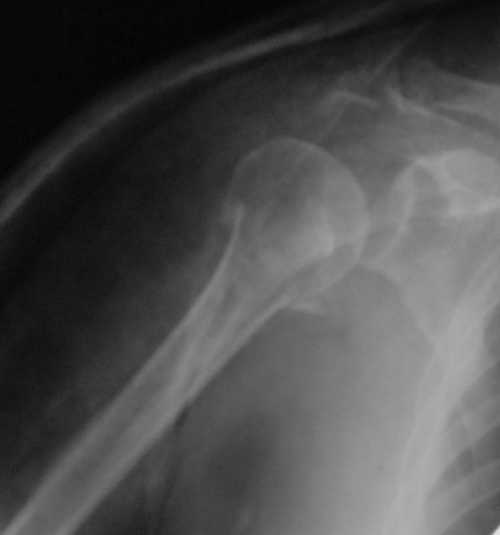

Снимки на 1-е сутки после репозиции и на 8- сутки после репозиции.

Пожалуйста

С ув. Sergey A. Melashenko, г. Запорожье